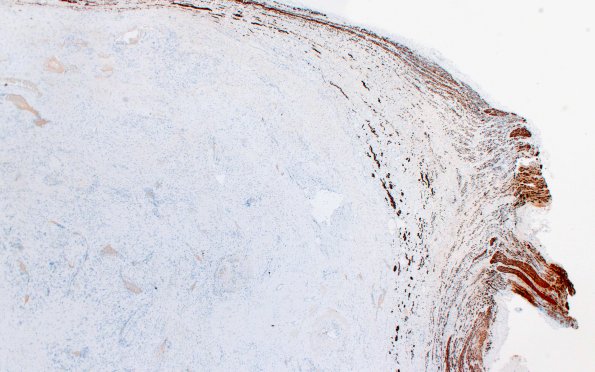

32E1 Schwannoma (Case 32) NF 2X

Axons in the parent nerve are splayed over the surface of the tumor. (NF IHC),